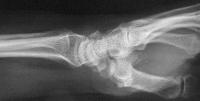

Palmar flexion of the scaphoid, lunate dorsiflexion.

Scapholunate diastasis.